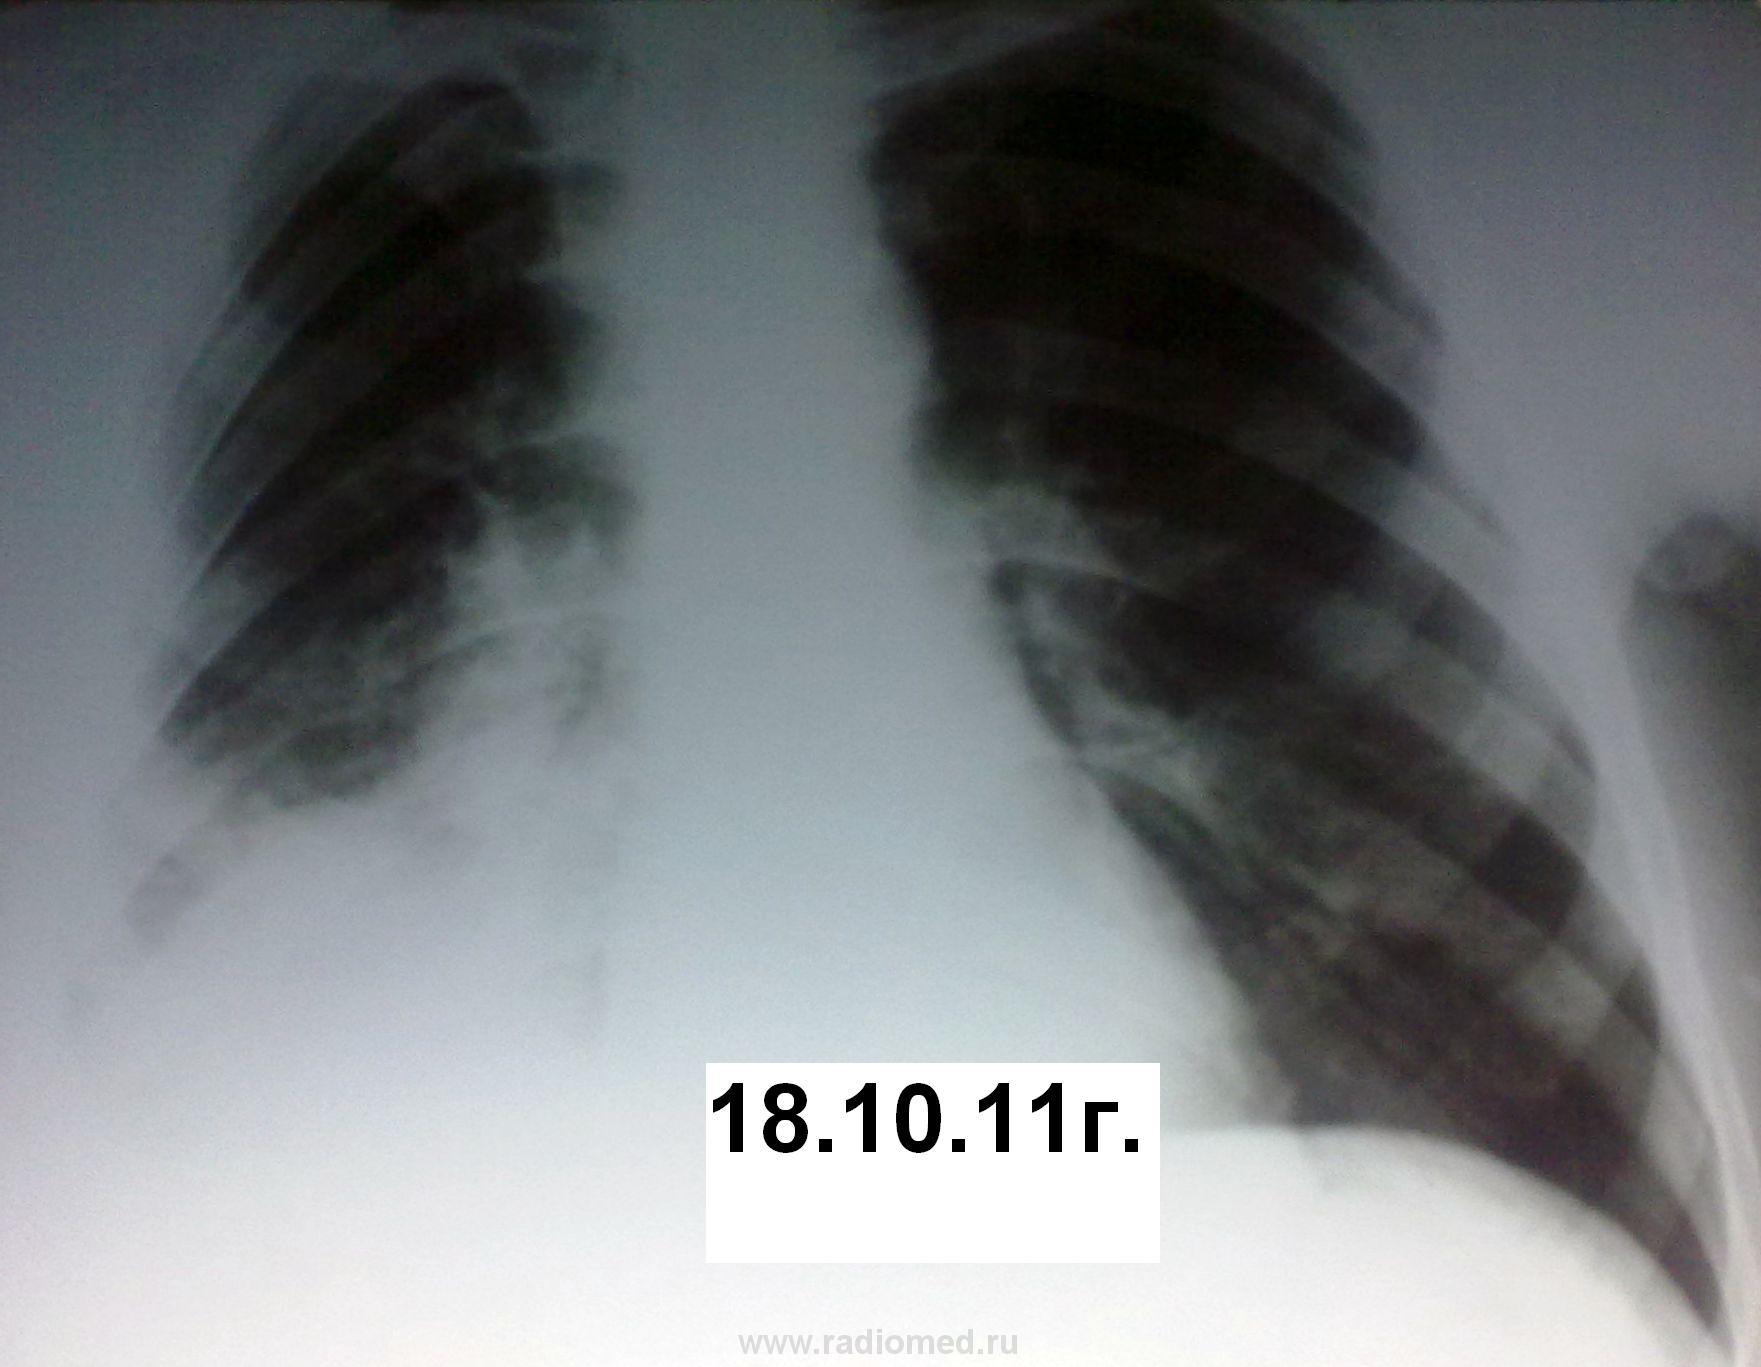

Вот такая динамика. Первый снимок я добыл позже. Между первым и вторым пациент лечил пневмонию в домашних условиях. В дальнейшем ее же в условиях стационара без финансовых и лекарственных ограничений.

Оказываетя, что за год до этого пациенту была удалена опухоль на бедре, гистологически синовиальная саркома. Было произведено КТ ОГК. Подтвердили пневмонию, мета в позвоночник.

Не зная, что была такая операция (больной вначале это притаил, видимо не хотел к этому возвращаться) я предположил БАР, но компъютерщики развеяли мои подозрения. Поэтому я бы хотел знатоков КТ-дела проанализировать сканы, все ли там в порядке с корнем и т.д.

Пневмонии тут нет никаким боком. Не было КТ - высказался бы за БАР. На КТ, в легких -типичный раковый лимфангаит (кстати, слева тоже, еще чуть-чуть и полыхнет). Так что, 100% метастазирование. И это кроме очевидного метастаза в позвонок. А корень надо оценивать в "медиастинальном" окне.